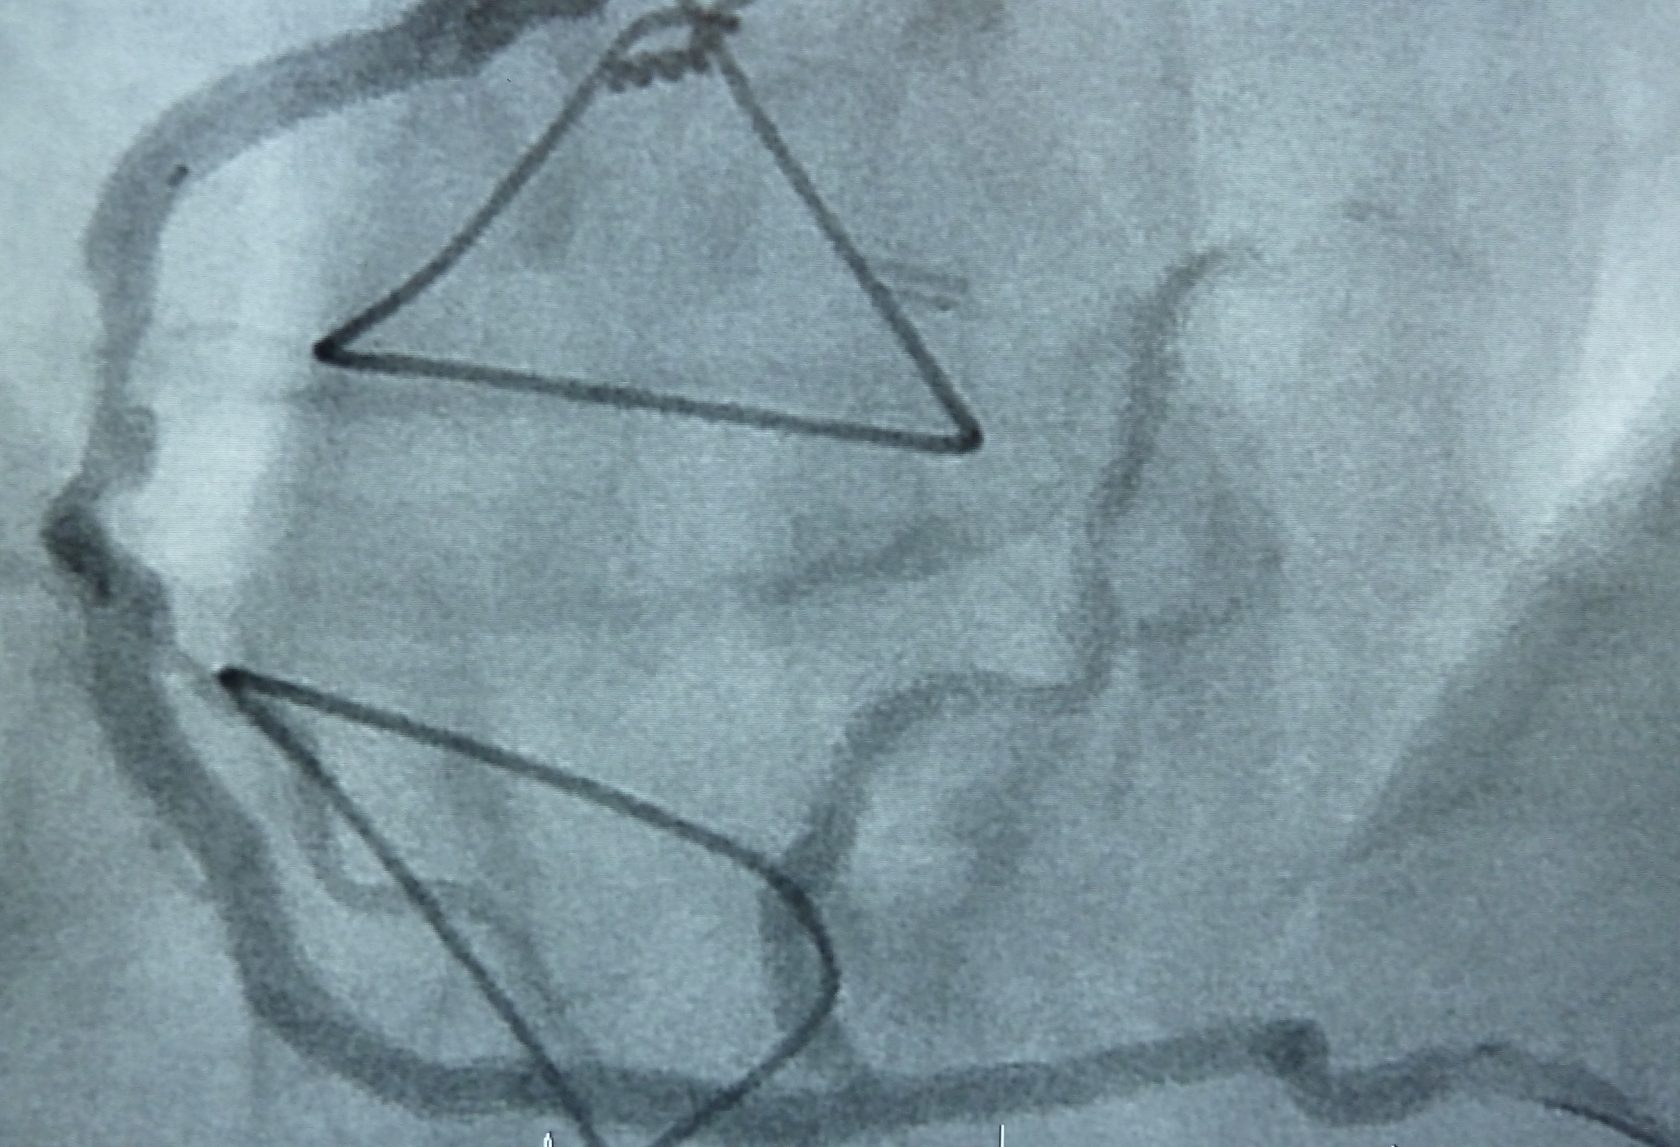

Die Stentimplantation ist ein Mittel zur Behandlung der Herzkranzgefäßerkrankung. Das Prinzip beruht darauf, dass eine Herzkranzgefäßverengung mittels Ballon aufgedehnt wird. Auflagerungen werden somit in die Gefäßwand gedrückt, wobei es zu einem Einreißen der Gefäßinnnenhaut kommen kann.

Der auf dem Ballon montierte Stent dehnt sich aus und hält das Gefäß in über 95% der Fälle dauerhaft offen. Damit wird die Durchblutung des Herzmuskels komplett wiederhergestellt.

Grundsätzlich ist das Vorgehen analog zur Herzkatheteruntersuchung. Vorbereitung und Einführung des Katheters geschehen wie dort geschildert. Es werden zunächst Medikamente zur Gerinnungshemmung und zur Erweiterung der Kranzarterien gespritzt. Durch den in der Kranzarterie liegenden Katheter wird nach Darstellung der Kranzarterie ein sehr weicher, flexibler Führungsdraht über die Kranzgefäßverengung vorgeführt. Über diesen als Leitschiene wird dann der eigentliche Ballonkatheter nachgeführt und der Ballon in der Verengung unter hohem Druck aufgeweitet. Sollte dies nicht gelingen, kann die Verengung auch mit einer speziellen Fräse abgetragen werden (Rotablation).

In den meisten Fällen ist auf dem Ballon direkt ein Stent (Gefäßstütze aus metallischem Maschenwerk) aufgesetzt, der durch die Dehnung in die Gefäßwand gepresst wird. Der Druck im Ballon wird entlastet und dieser entfernt. Der Stent bleibt lebenslang im Gefäß und wächst innerhalb Monaten ein. Nach Kontrolle durch Darstellung des Gefäßes wird der Katheter und die Schleuse entfernt.